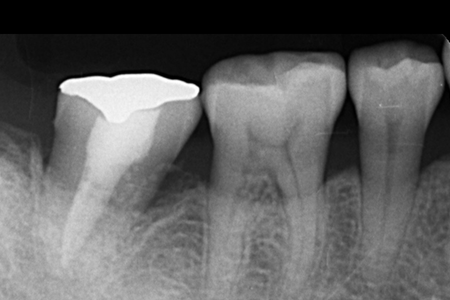

治療名 【歯周・歯内複合病変】組織再生療法+精密根管治療 治療期間 約1年 執刀医 Dr. 大杉 治療費 420,000円(税込)

■内訳:

再生療法 250,000円

根管治療 130,000円

支台築造 40,000円治療解説 歯の内部と歯周組織の両方に感染が及んでおり、抜歯判断になりやすいケースに対して保存を前提に治療を行いました。

まず精密根管治療で感染源を除去・封鎖し、その後に歯周組織再生療法を実施。

内外の感染を段階的にコントロールすることで、抜歯回避と安定化を目指しました。リスク・副作用 神経(歯髄)を除去するため、歯への栄養供給が断たれ、健全歯に比べて強度が低下します。

硬いものを噛んだ際などに歯根破折のリスクが伴う。 -